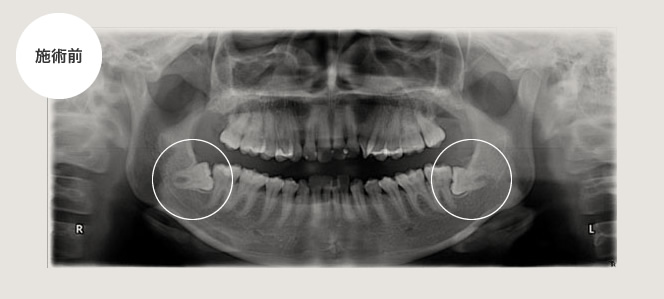

腫れが強い場合

左下が腫れて痛いという主訴で来院され、その日は抗生剤の投与及び消毒をして1週間後に腫れが減少してから抜きました。時間は約30分ぐらいで比較的術後の腫れもなかったです。

その後患者さんからこれぐらいの腫れと痛みならということで、3ヵ月後に右下の親知らずも抜いてくれということで、抜きました。

所要時間は約30分で術後の腫れも前回と同じくらいとのことでした。